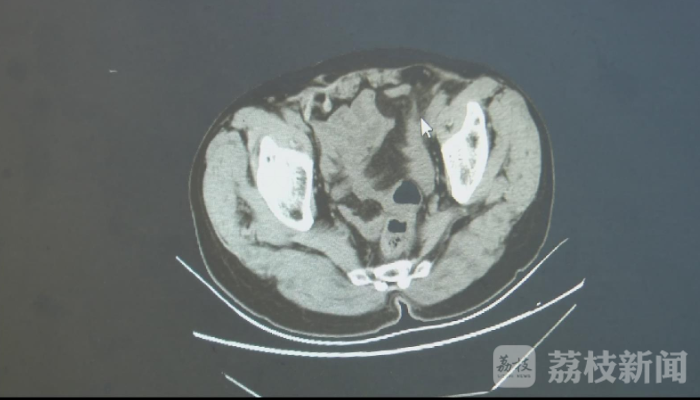

通过CT检查,医生很快发现了陈大爷肚子痛的根源,原来是鱼刺将大肠给刺穿了。医生介绍,乙状结肠主要用于存放大便,肠壁被刺穿后大便就会流入腹腔,危急生命。11月9日凌晨三点,医生紧急为陈大爷实施了手术,将鱼刺顺利取出。目前,陈大爷术后情况良好。